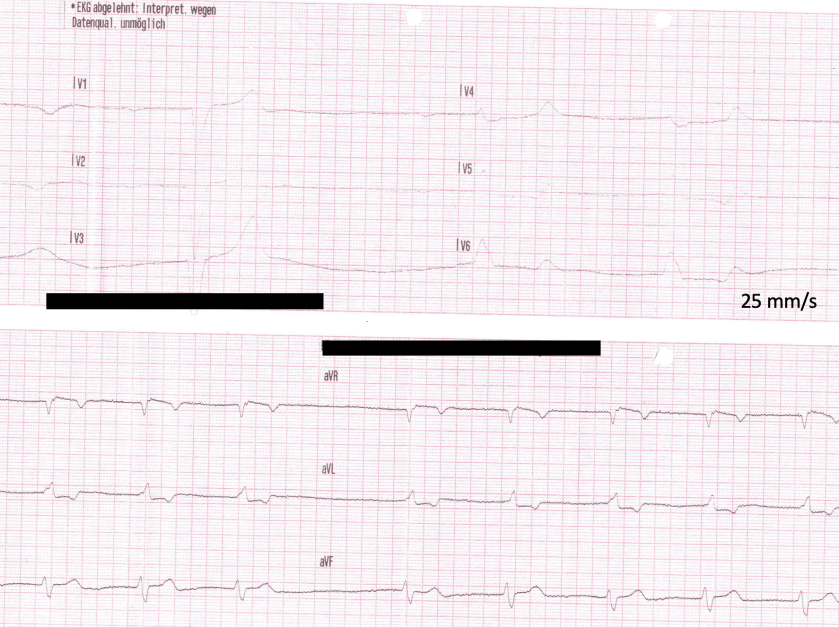

image-10